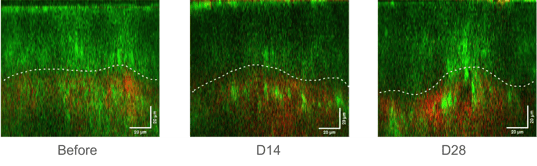

◆シワやたるみに対する作用

シワやたるみに関連するコラーゲン線維とエラスチン線維を、画像解析することで強度や回復度合いを相対比較します。

また、定性的にも、線維の太さや方向性を観察することで、サンプル使用による肌状態の変化を捉えることができます。

◆肌老化に対する作用

表皮真皮接合部(下図の点線、表皮と真皮の界面)を観察することで、 肌老化の指標として活用できる可能性があります。